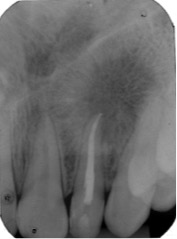

Dens in dente is a dental development malformation that involves more commonly the upper lateral incisors. Infection of the canal of these teeth can cause the formation of chronic periapical lesions. The present study aimed to describe an integrated approach between the endodontic therapy and surgical intervention in an upper lateral incisor with dens in dente type II. A female patient, 14 years old, looked for dental care complaining of left palatal and paranasal bulging. Clinical, radiological and histopathological findings suggested periradicular cyst. First, marsupialization was performed to reduce the size of the lesion and to favor its enucleation, with less risk of injuring the tooth and vital structures. After diagnosis of pulp necrosis and in attempt to reduce the infection via canal, we used the reciprocating instrumentation associated with irrigation with sodium hypochlorite, intracanal medication based on calcium hydroxide and filled with a thermoplastic filling. After a year of marsupialization, fistulectomy and complete enucleation of the lesion were performed. Proservation was performed 1, 3, 6 and 12 months following marsupialization. Six months after enucleation, we observed the periradicular repair and remission of symptoms. The extensive apical lesion associated with dens in dente type II can be treated with a combination of surgical and endodontic therapy.